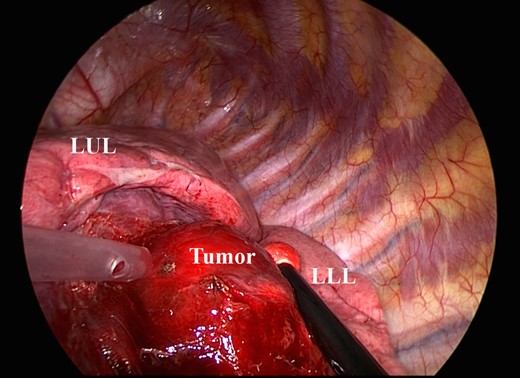

The patient was anesthetized with general anesthesia, intubated with a double-lumen endotracheal tube intubation and placed in a left lateral decubitus position. A 5-cm utility minithoracotomy was placed in the fifth intercostal space (ICS), and two ports were placed in the eighth ICS at the middle and posterior axillary lines. All procedures were performed under thoracoscopic view. The pericardium was defective, and the epicardium was exposed to the pleural cavity. There was direct adhesion between the exposed heart and lung; therefore, dissection of the adhesion was performed with great caution (Fig. 2). The tumor was predominantly located in the lower lobe, over the left major fissure, and spreads to the left upper lobe (Fig. 3). We decided to perform tumor enucleation, because the tumor was diagnosed as inflammatory or fibrotic upon intraoperative frozen section examination. Because of a severe adhesion surrounding the left pulmonary hilum, it was considered too difficult to tape the left main PA immediately after bleeding from the interlobar PA. First, the left upper pulmonary vein was encircled and pulled caudally (Fig. 4). Then, the left main PA was encircled prior to enucleation to prepare for the emergent bleeding. This procedure was performed through an additional anterolateral minithoracotomy (3 cm) in the third ICS. An adhesion surrounding the left PA was especially severe and very difficult to dissect. The vascular tape encircling the left main PA was extracted to outside of the pleural cavity through the additional minithoracotomy, and we prepared for clamping when needed. Then, tumor enucleation was performed. An adhesion between the tumor and the interlobar PA was safely dissected. We could control an air leakage by using a polyglycolic acid sheet and fibrin glue, because it was observed only from the parenchyma of the interlobar surface. There were no intraoperative complications.

The tumor is located predominantly in the lower lobe, over the left major fissure, and spreads to the left upper lobe. LUL, left upper lobe; LLL, left lower lobe.